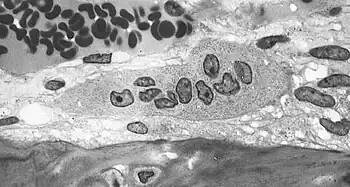

Osteoclast cells

Osteoclasts are located on the surface of bones and form resorption pits by excreting H+ to the bone surface removing hydroxyapatite, multiple bone minerals, and organic components: collagen and dentin. The purpose of bone resorption is to release calcium to the blood stream for various life processes.[17] These resorption pits are visible under electron microscopy and distinctive trails are formed from prolonged resorption. Osteoclasts have shown to be "absolutely dependent on extracellular acidification".[14] A drop in pH of <0.1 units can cause a 100% increase in osteoclast cell activity, this effect persists with prolonged acidosis with no desensitization, "amplifying the effects of modest pH differences". Osteoclast cells show little or no activity at pH 7.4 and are most active at pH 6.8 but can be further stimulated by other factors such as parathyroid hormone.[16]